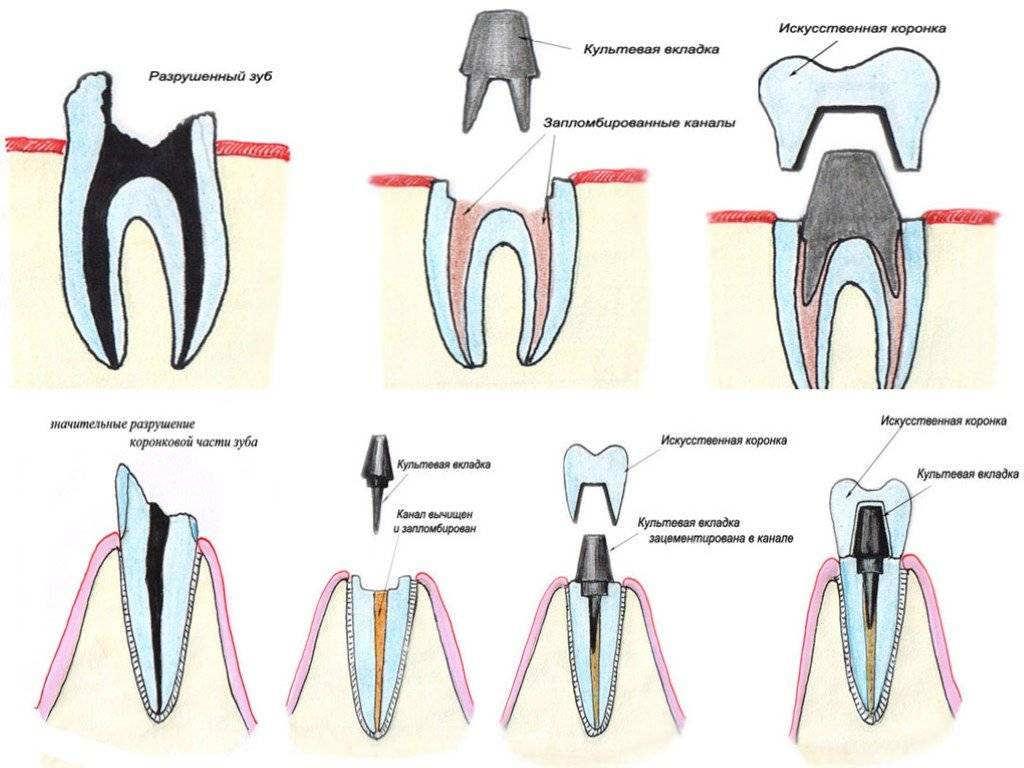

Культя зуба это

Культя зуба это 106 фото